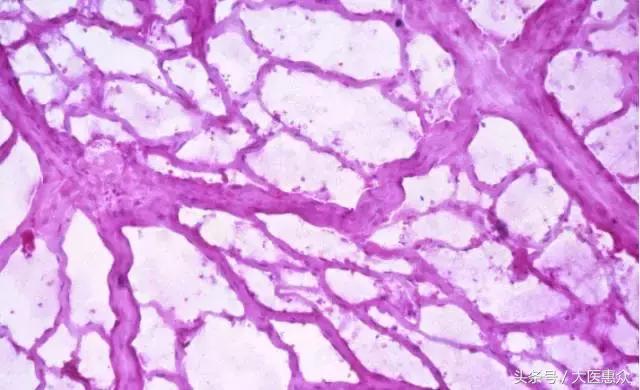

运动锻炼能使人体血浆容量相对增加,从而促使更多的血液水分贮留在血液循环中,通过改善微循环,使子宫动脉血流量增加,血流速度加快,从而很好地缓解子宫缺血情况,以缩短子宫收缩的时间,达到解除与缓解痛经症状的目的。